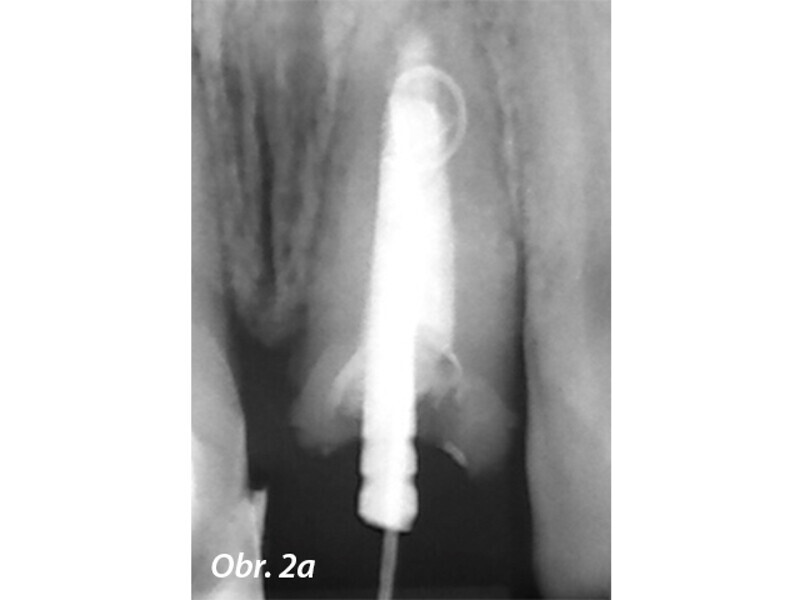

Aplikace MTA s použitím Produit Dentaires (PD) MAP System